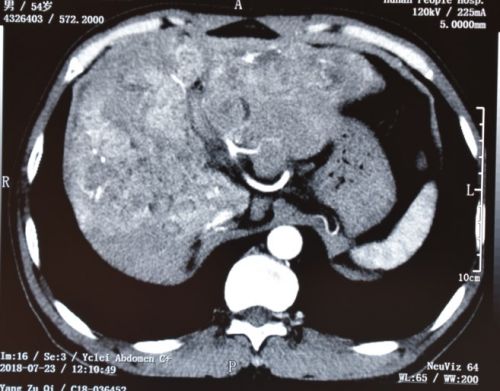

术前ct可以看到肝内充满结石。

入院完善相关检查后,齐忠良被诊断为“肝胆管结石、胆道梗阻、胆源性肝硬化、右后叶胆管狭窄”。从CT片上可以看到,他的整个肝脏布满结石,最大的石头直径有50mm;同时左肝肥大、右肝萎缩,肝内胆管极度扩张——原本直径只有5~6mm的胆管,最粗直径竟然达到30mm。不仅如此,齐忠良的胆管先天变异——右肝管缺如,右后叶胆管开口在左肝管上。如果不及时手术,病情进一步发展,将导致胆道休克、肝昏迷、肝衰竭,危及生命。